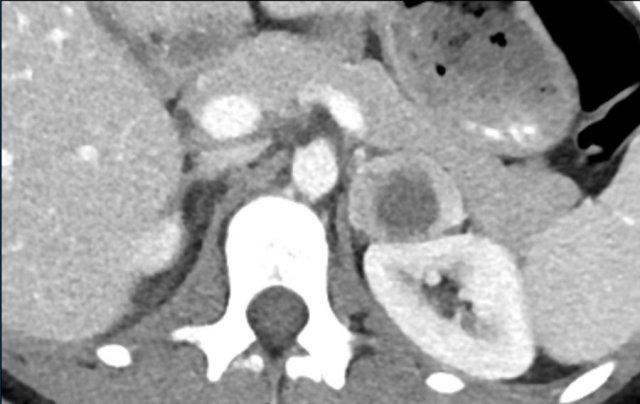

Đây là tổn thương không xác định, ngấm thuốc không đồng nhất, bờ tương đối rõ.

Tổn thương được xác định là u tủy thượng thận (pheochromocytoma).

Tổn thương tuyến thượng thận ngấm thuốc mạnh kích thước 7 cm với các ổ nang nhỏ.

Tổn thương được phẫu thuật cắt bỏ do kích thước lớn và đặc điểm hình ảnh không xác định.

Kết quả mô bệnh học xác định đây là u tuyến (adenoma).